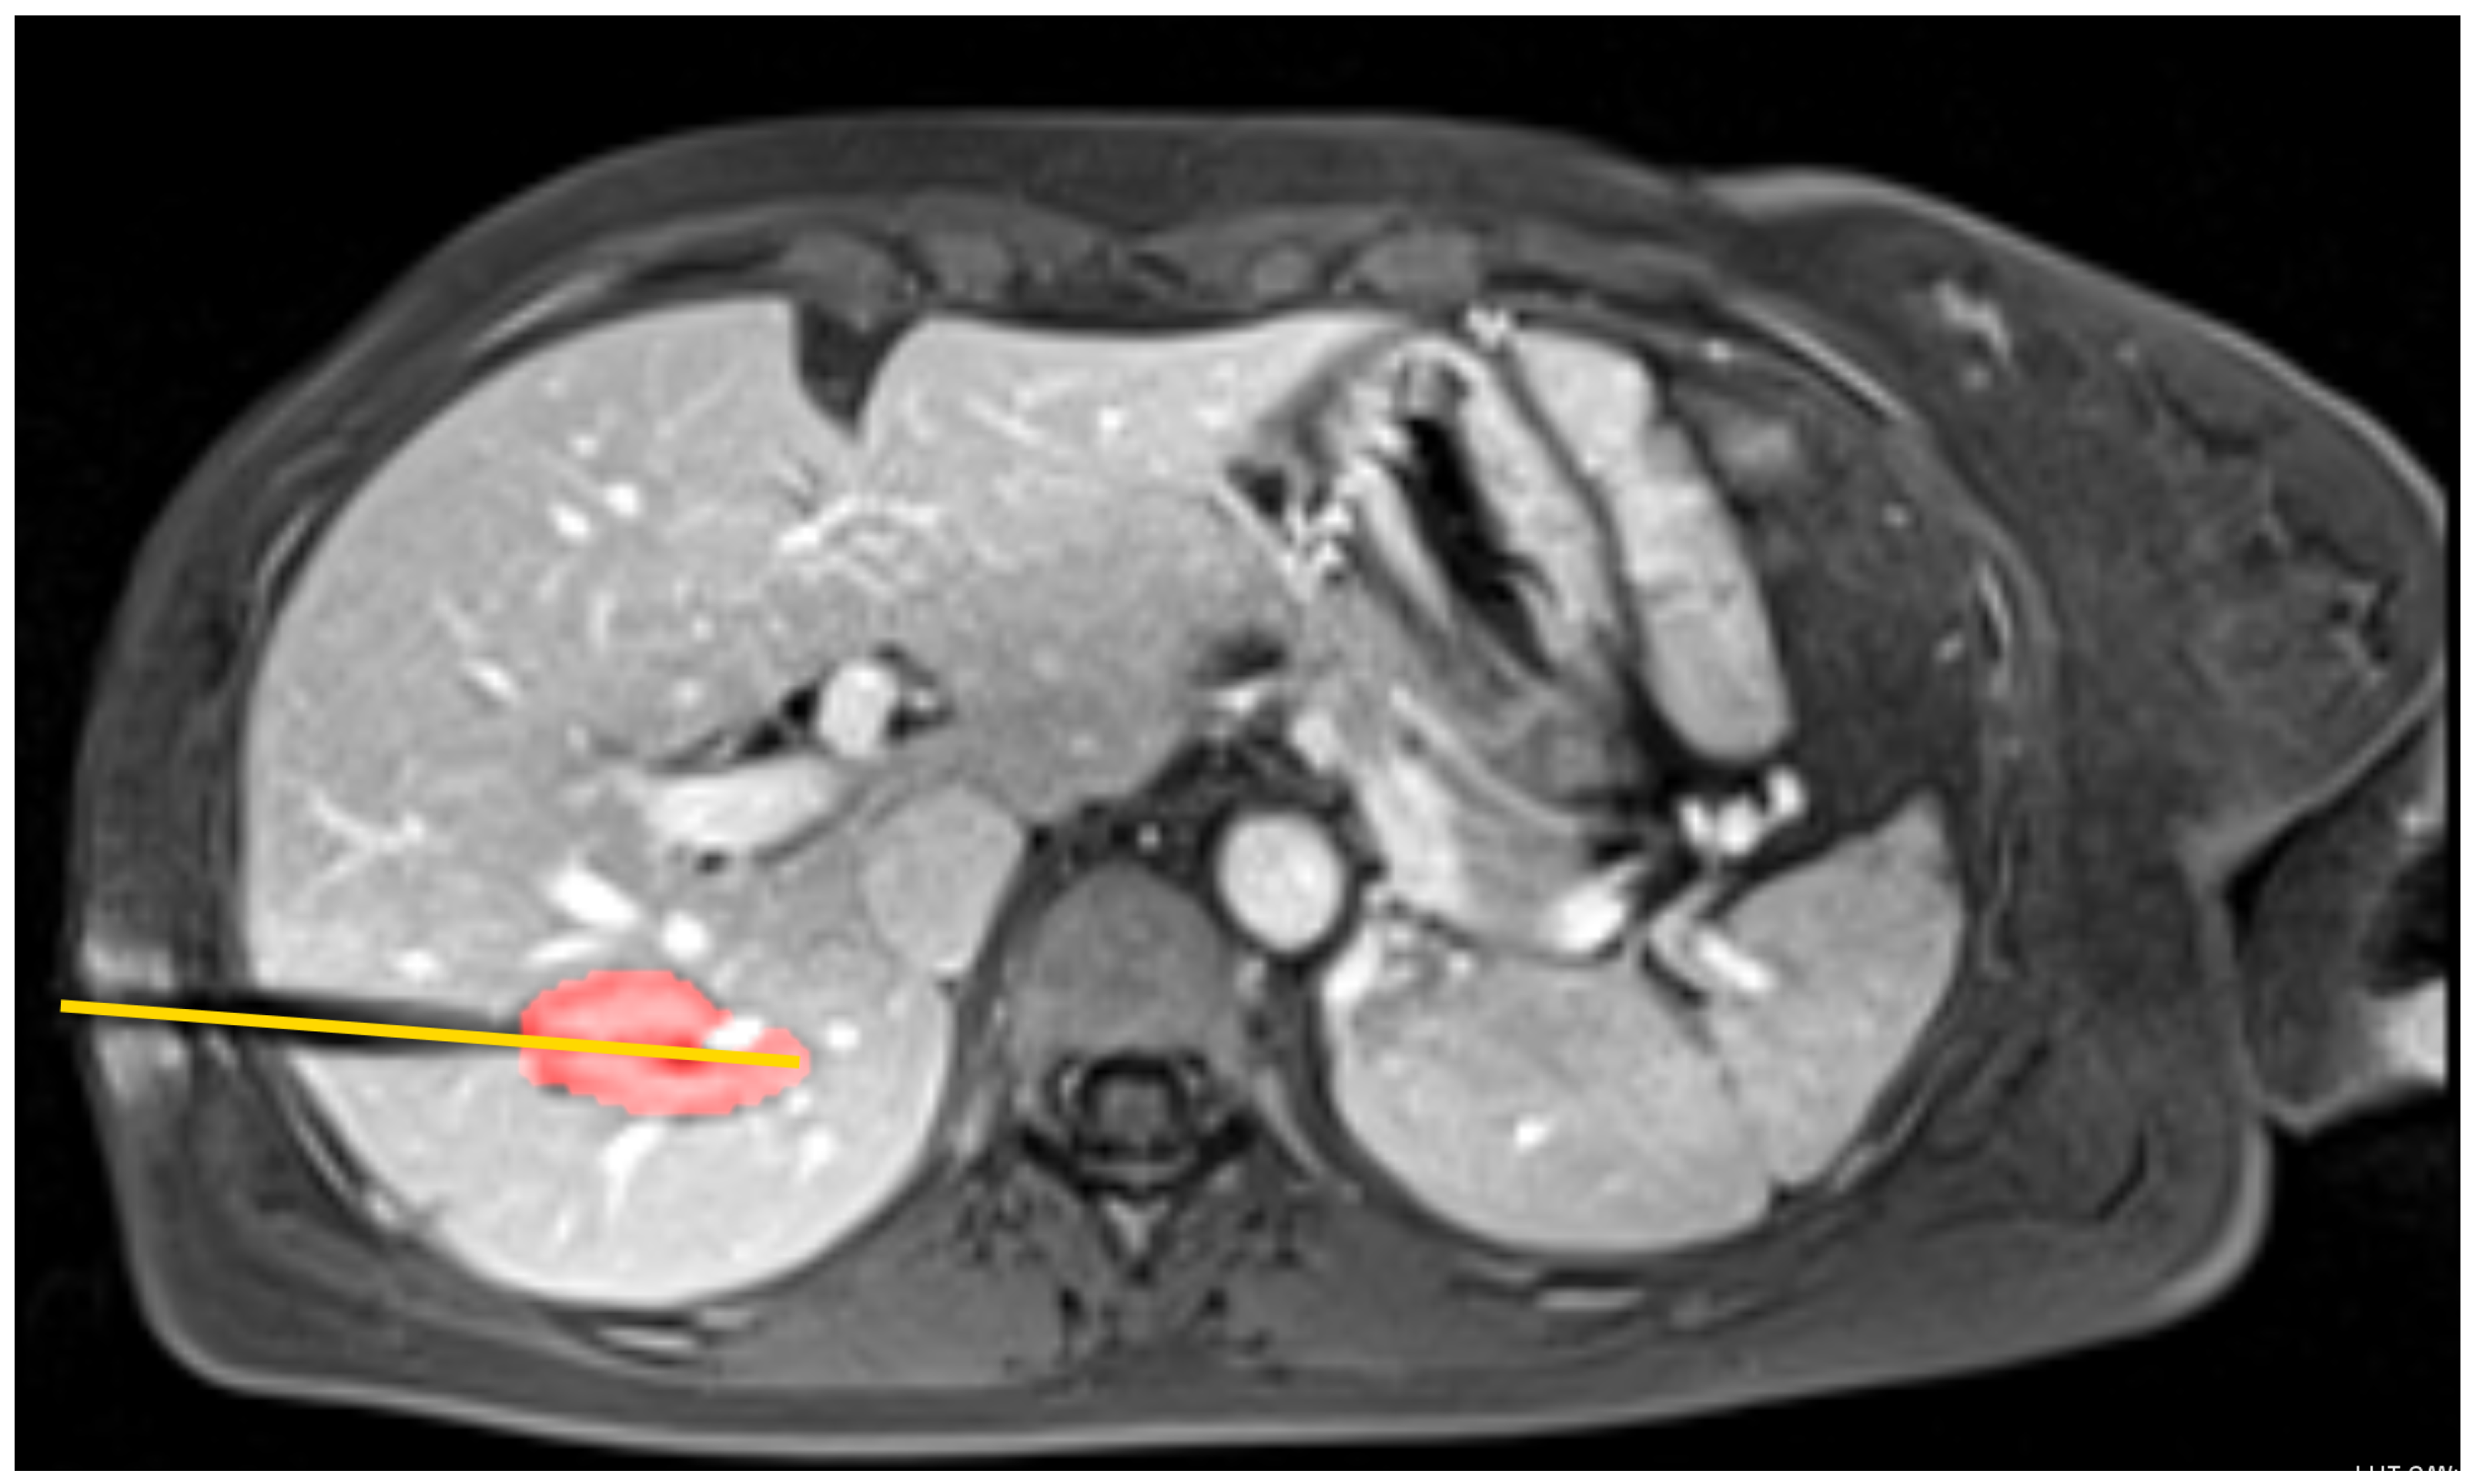

3.2. Clinical Case